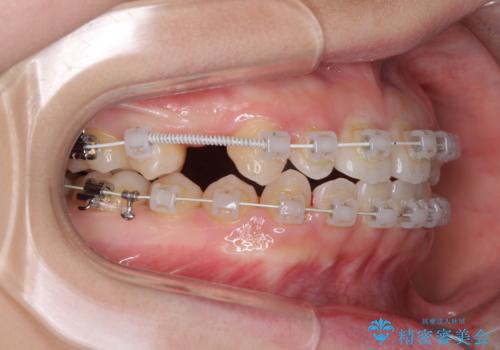

インビザラインによる矯正治療も提案しましたが、長時間の装着や自己管理が難しいとお考えで、ワイヤーによる矯正治療を行いました。

歯並びは比較的早めに整いましたが、インプラントを埋入するにあたって前後の歯根位置を改善する必要があり、矯正治療に期間を要することとなりました。